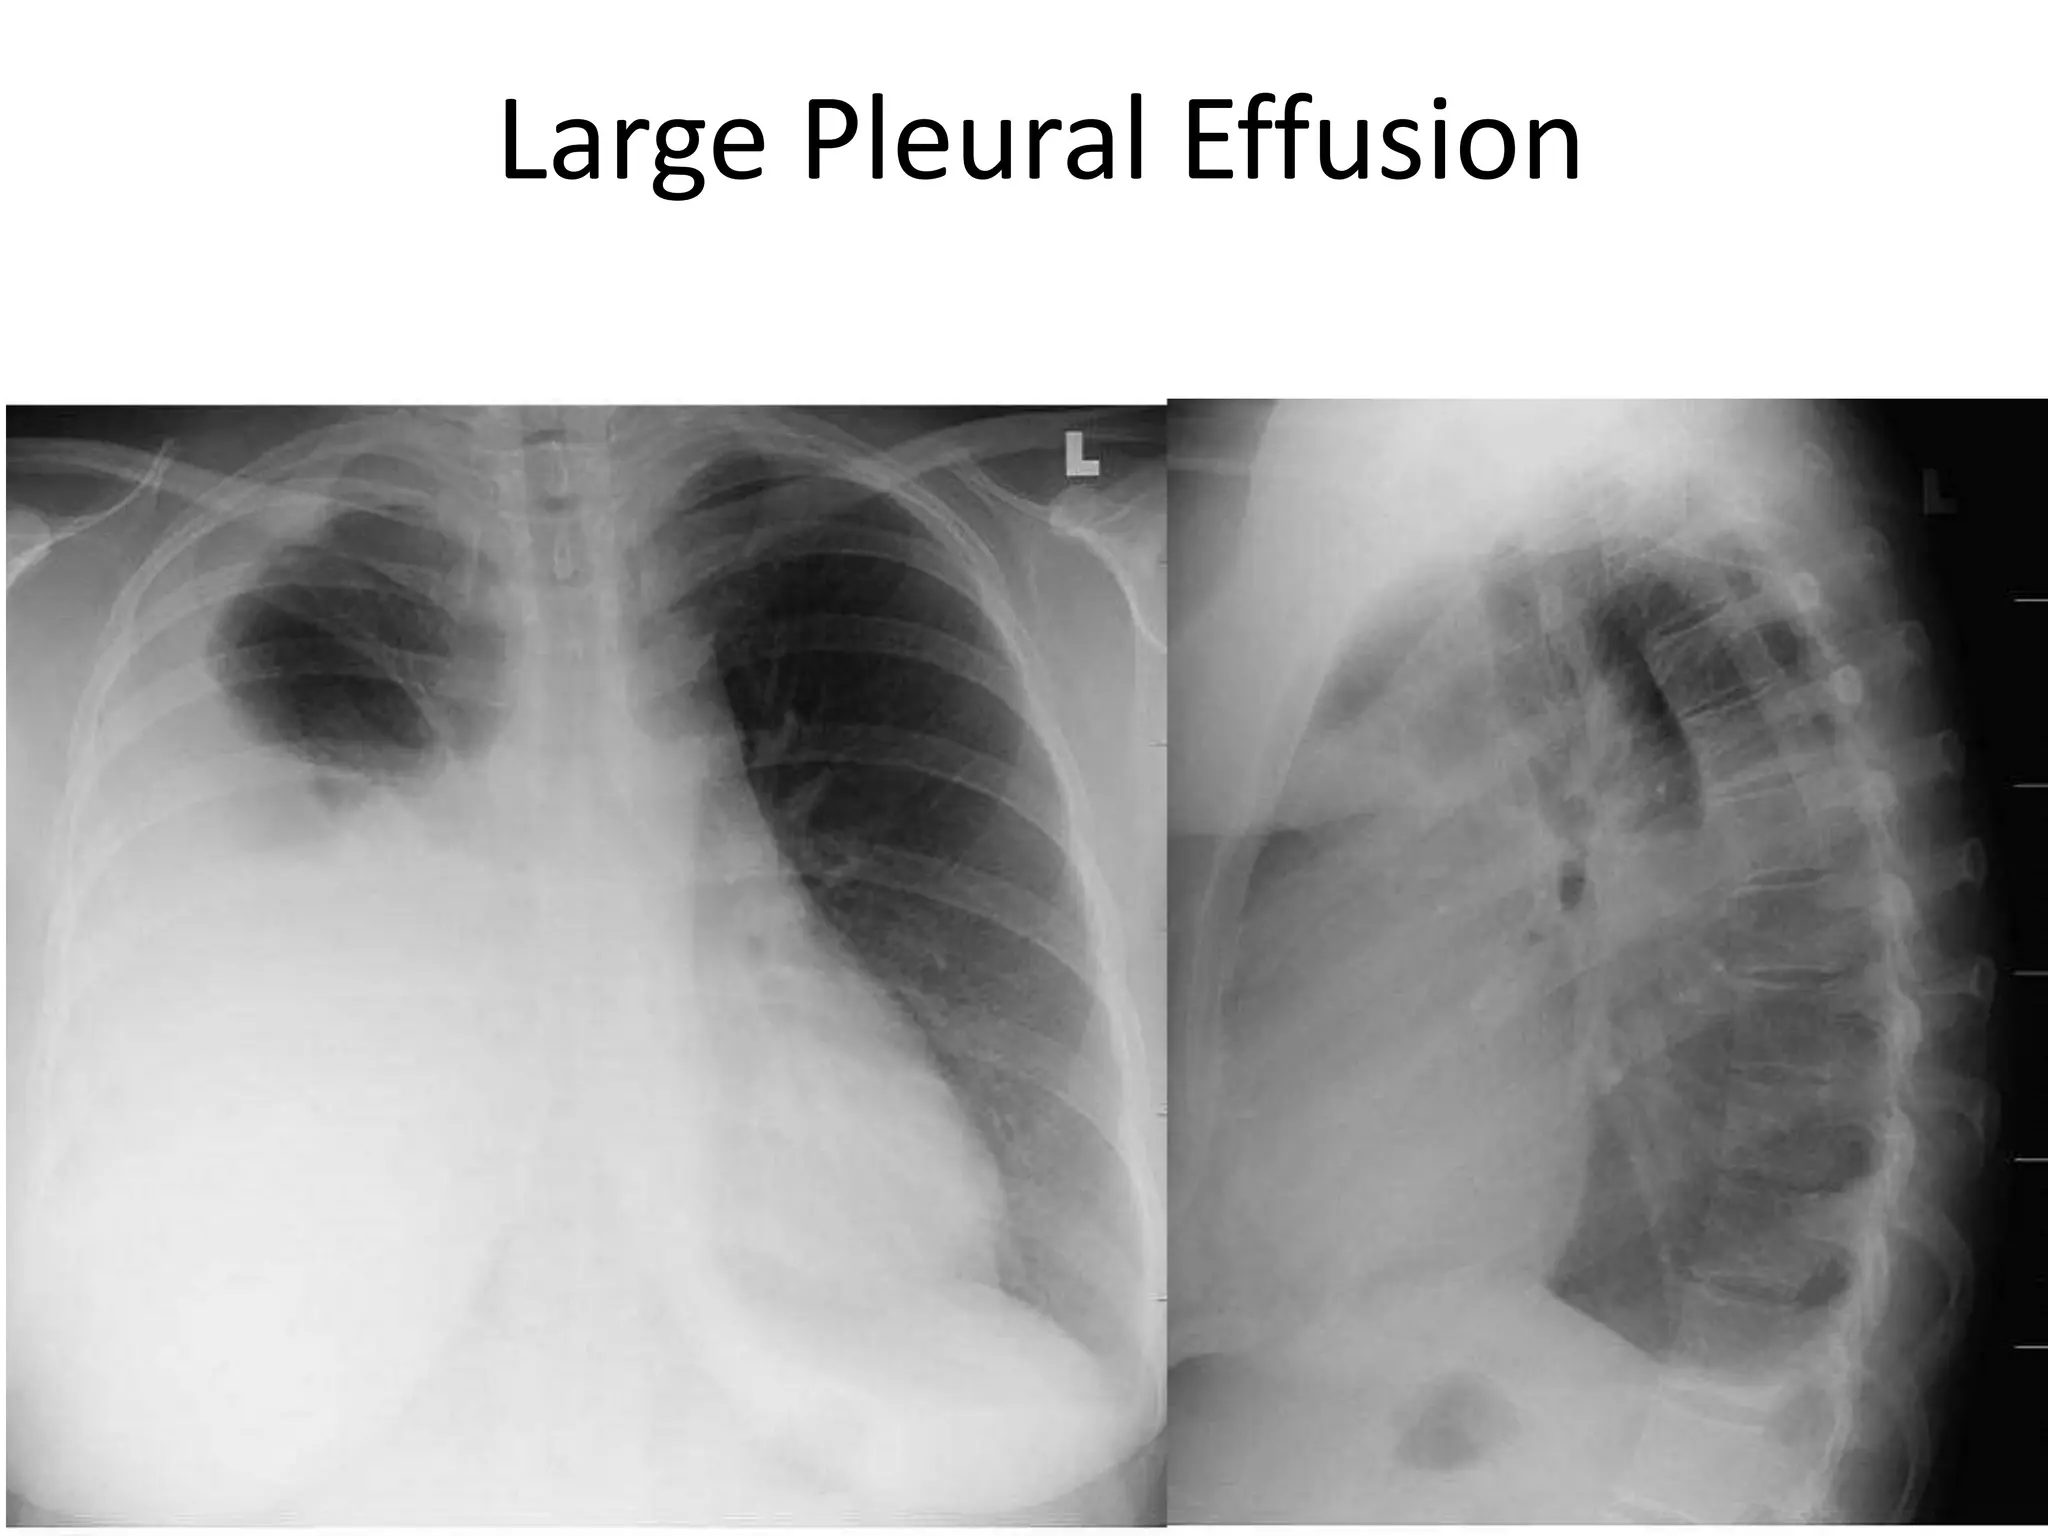

• Chest X-ray PA view showing dense

homogenous opacity at the Rt lung base with

curved upper border, blunting the

costophrenic angle and ascending towards the

axilla. Suggestive of Rt Pleural Effusion

• Around 200 mL of fluid is required in order for

it to be detectable on a PA chest X-ray.

Pleural Effusion

• Figure 10.17

• Chest X-ray showing a

large left pleural effusion

in a young man with a 4-

month history of malaise,

fever, night sweats and

weight loss. The diagnosis

of tuberculosis was

confirmed on histology of

a pleural biopsy and

culture of the pleural

fluid.